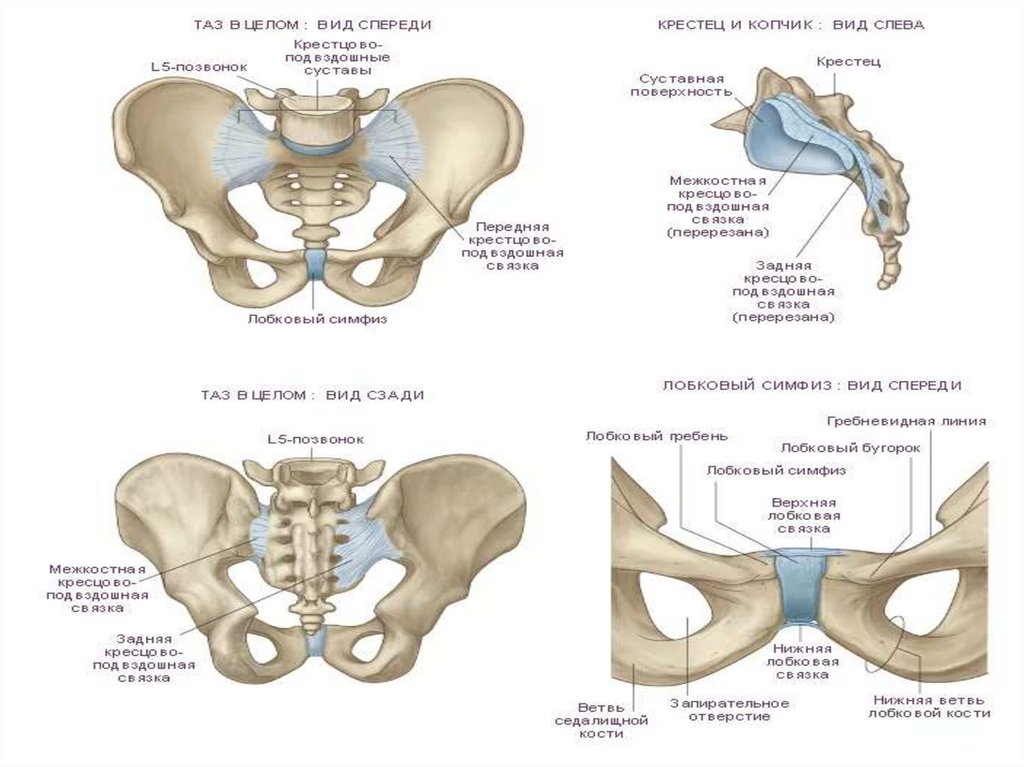

Анатомия малого таза: детальные схемы и изображения

Раздел: Образы вокруг